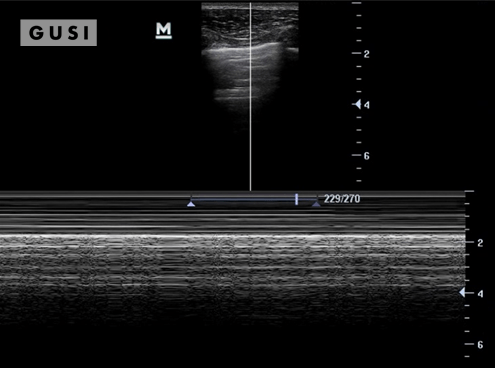

During the 2018 World Taekwondo Junior Championships in Hammamet, Tunisia, a 17-year-old male junior Taekwondo athlete took a fall, landing on his right shoulder. He exhibited a markedly limited range of motion in the affected shoulder and experienced intense pain, leading to suspicions of a dislocation.

A pre-reduction ultrasound (A) of the right shoulder showed a pronounced gap between the humeral head (indicated by a solid arrow) and the glenoid (marked by an open arrow), suggesting an anterior dislocation. Following a shoulder reduction procedure, a post-reduction ultrasound (B) verified the successful realignment of the glenohumeral joint (solid arrow pointing to the humeral head and open arrow to the glenoid).

After the procedure, the athlete displayed a considerably improved range of motion in his right shoulder and his pain levels diminished significantly.